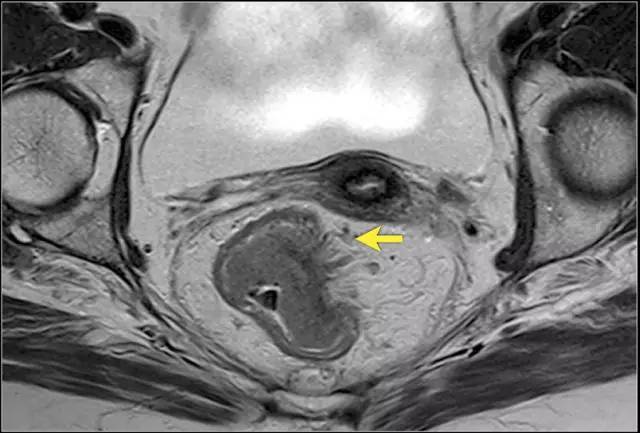

图 14 轴向 T2 加权图像上,沿着内脏腹膜有肿瘤向内生长(箭头)